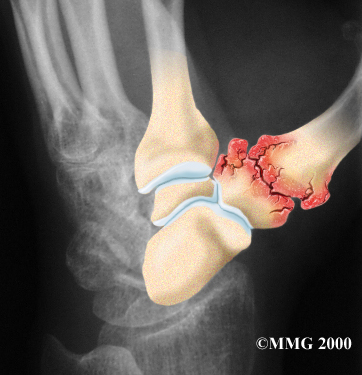

Several ligaments hold the CMC joint together. These ligaments can be injured, such as when you sprain your thumb. The joint surfaces are covered with a material called articular cartilage. This material is the slick, spongy covering that allows one side of a joint to slide against the other joint surface easily.

Articular Cartilage

Degenerative Arthritis

Injury to a joint, such as a bad sprain or fracture, can cause damage to the articular cartilage. An injury to the CMC joint of the thumb, even if it does not injure the articular cartilage directly, can alter how the joint works. After a fracture of the thumb metacarpal, the bone fragments may heal in slightly different positions. The joints may then line up differently. This is also true when the ligaments around the CMC joint are damaged by a sprain. When an injury results in a change in the way the joint moves, the injury may increase the forces on the articular cartilage surfaces. This is similar to any mechanical device or machinery. If the mechanism is out of balance, it tends to wear out faster.

Over many years this imbalance in the joint mechanics can lead to damage on the articular surface. Since articular cartilage cannot heal itself very well, the damage adds up. Eventually, the joint is no longer able to compensate for the increasing damage, and it begins to hurt. Damage has occurred well before the pain begins.